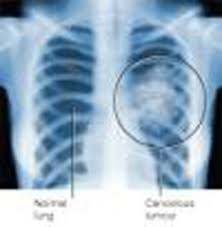

The mesothelioma is a type of cancer, the cells, mesothelial all the chest and abdomen. Mesothelioma is a rare, but it seems, is growing. Around 2000 to 3000 new cases of mesothelioma are diagnosed each year in the U.S. only. The symptoms of these two types of mesothelioma are not specifically for this disease, and often not diagnosed or wrongly diagnosed with a lot of time. Shortness of breath, chest and abdominal pain, fever and can be extended to other causes, so that this cancer has plenty of time to just before the diagnosis is usually seen. Because of difficulties in diagnosis of lung cancer, the survival rate after diagnosis is about one year.

The rise in mesothelioma is in four steps. These measures provide a basis for the planning of the measure on to cancer. Staging is based on X-rays, computed tomography and magnetic resonance imaging. Decisions about the treatment and the prognosis depends on the stage of mesothelioma, as well as the type when the mesothelioma. In the first stage, the mesothelioma in the pleura, the lung, the pericardium, or diaphragm, and is located on the side of the body. Mesothelioma penetrates the chest wall or the esophagus in the second phase. The second step may also be cancer in the heart, the two parts of the pleura, or in the lymph nodes in the chest. The third step is the penetration through the membrane and in the peritoneum, and believes that the cancer has spread to the lymph nodes. The fourth and final step occurs when the evidence shows metastases in distant organs. In the fourth stage mesothelioma through the blood to the new attractions.